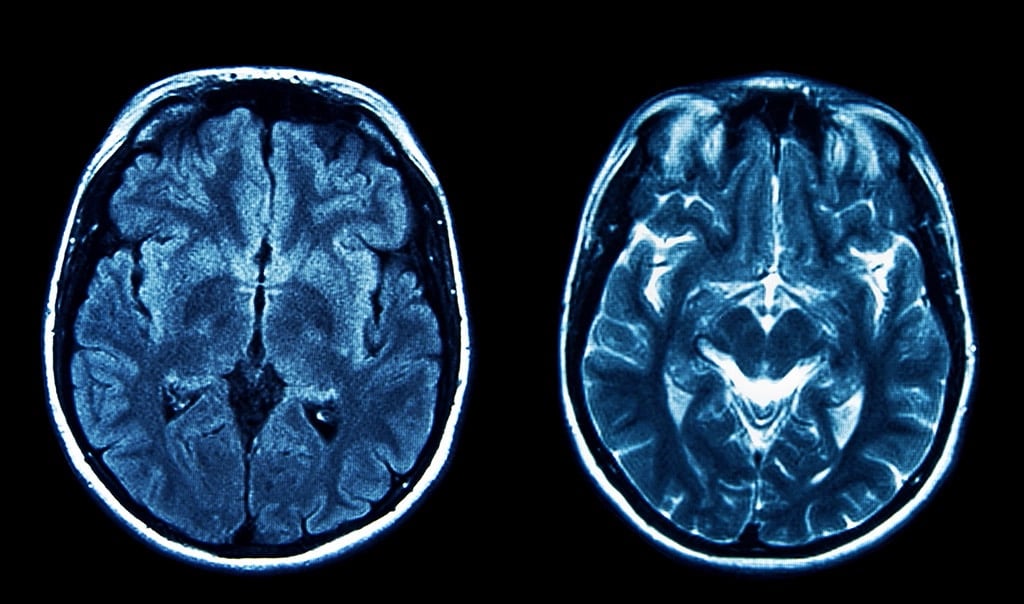

Dementia diagnosis involves a comprehensive medical assessment that begins with a detailed medical history and a physical examination. Cognitive tests and brain imaging, such as MRI or CT scans, may also be used to assess the extent of damage to the brain. Blood tests are often conducted to rule out other conditions that may mimic dementia symptoms, such as thyroid disorders or vitamin deficiencies.